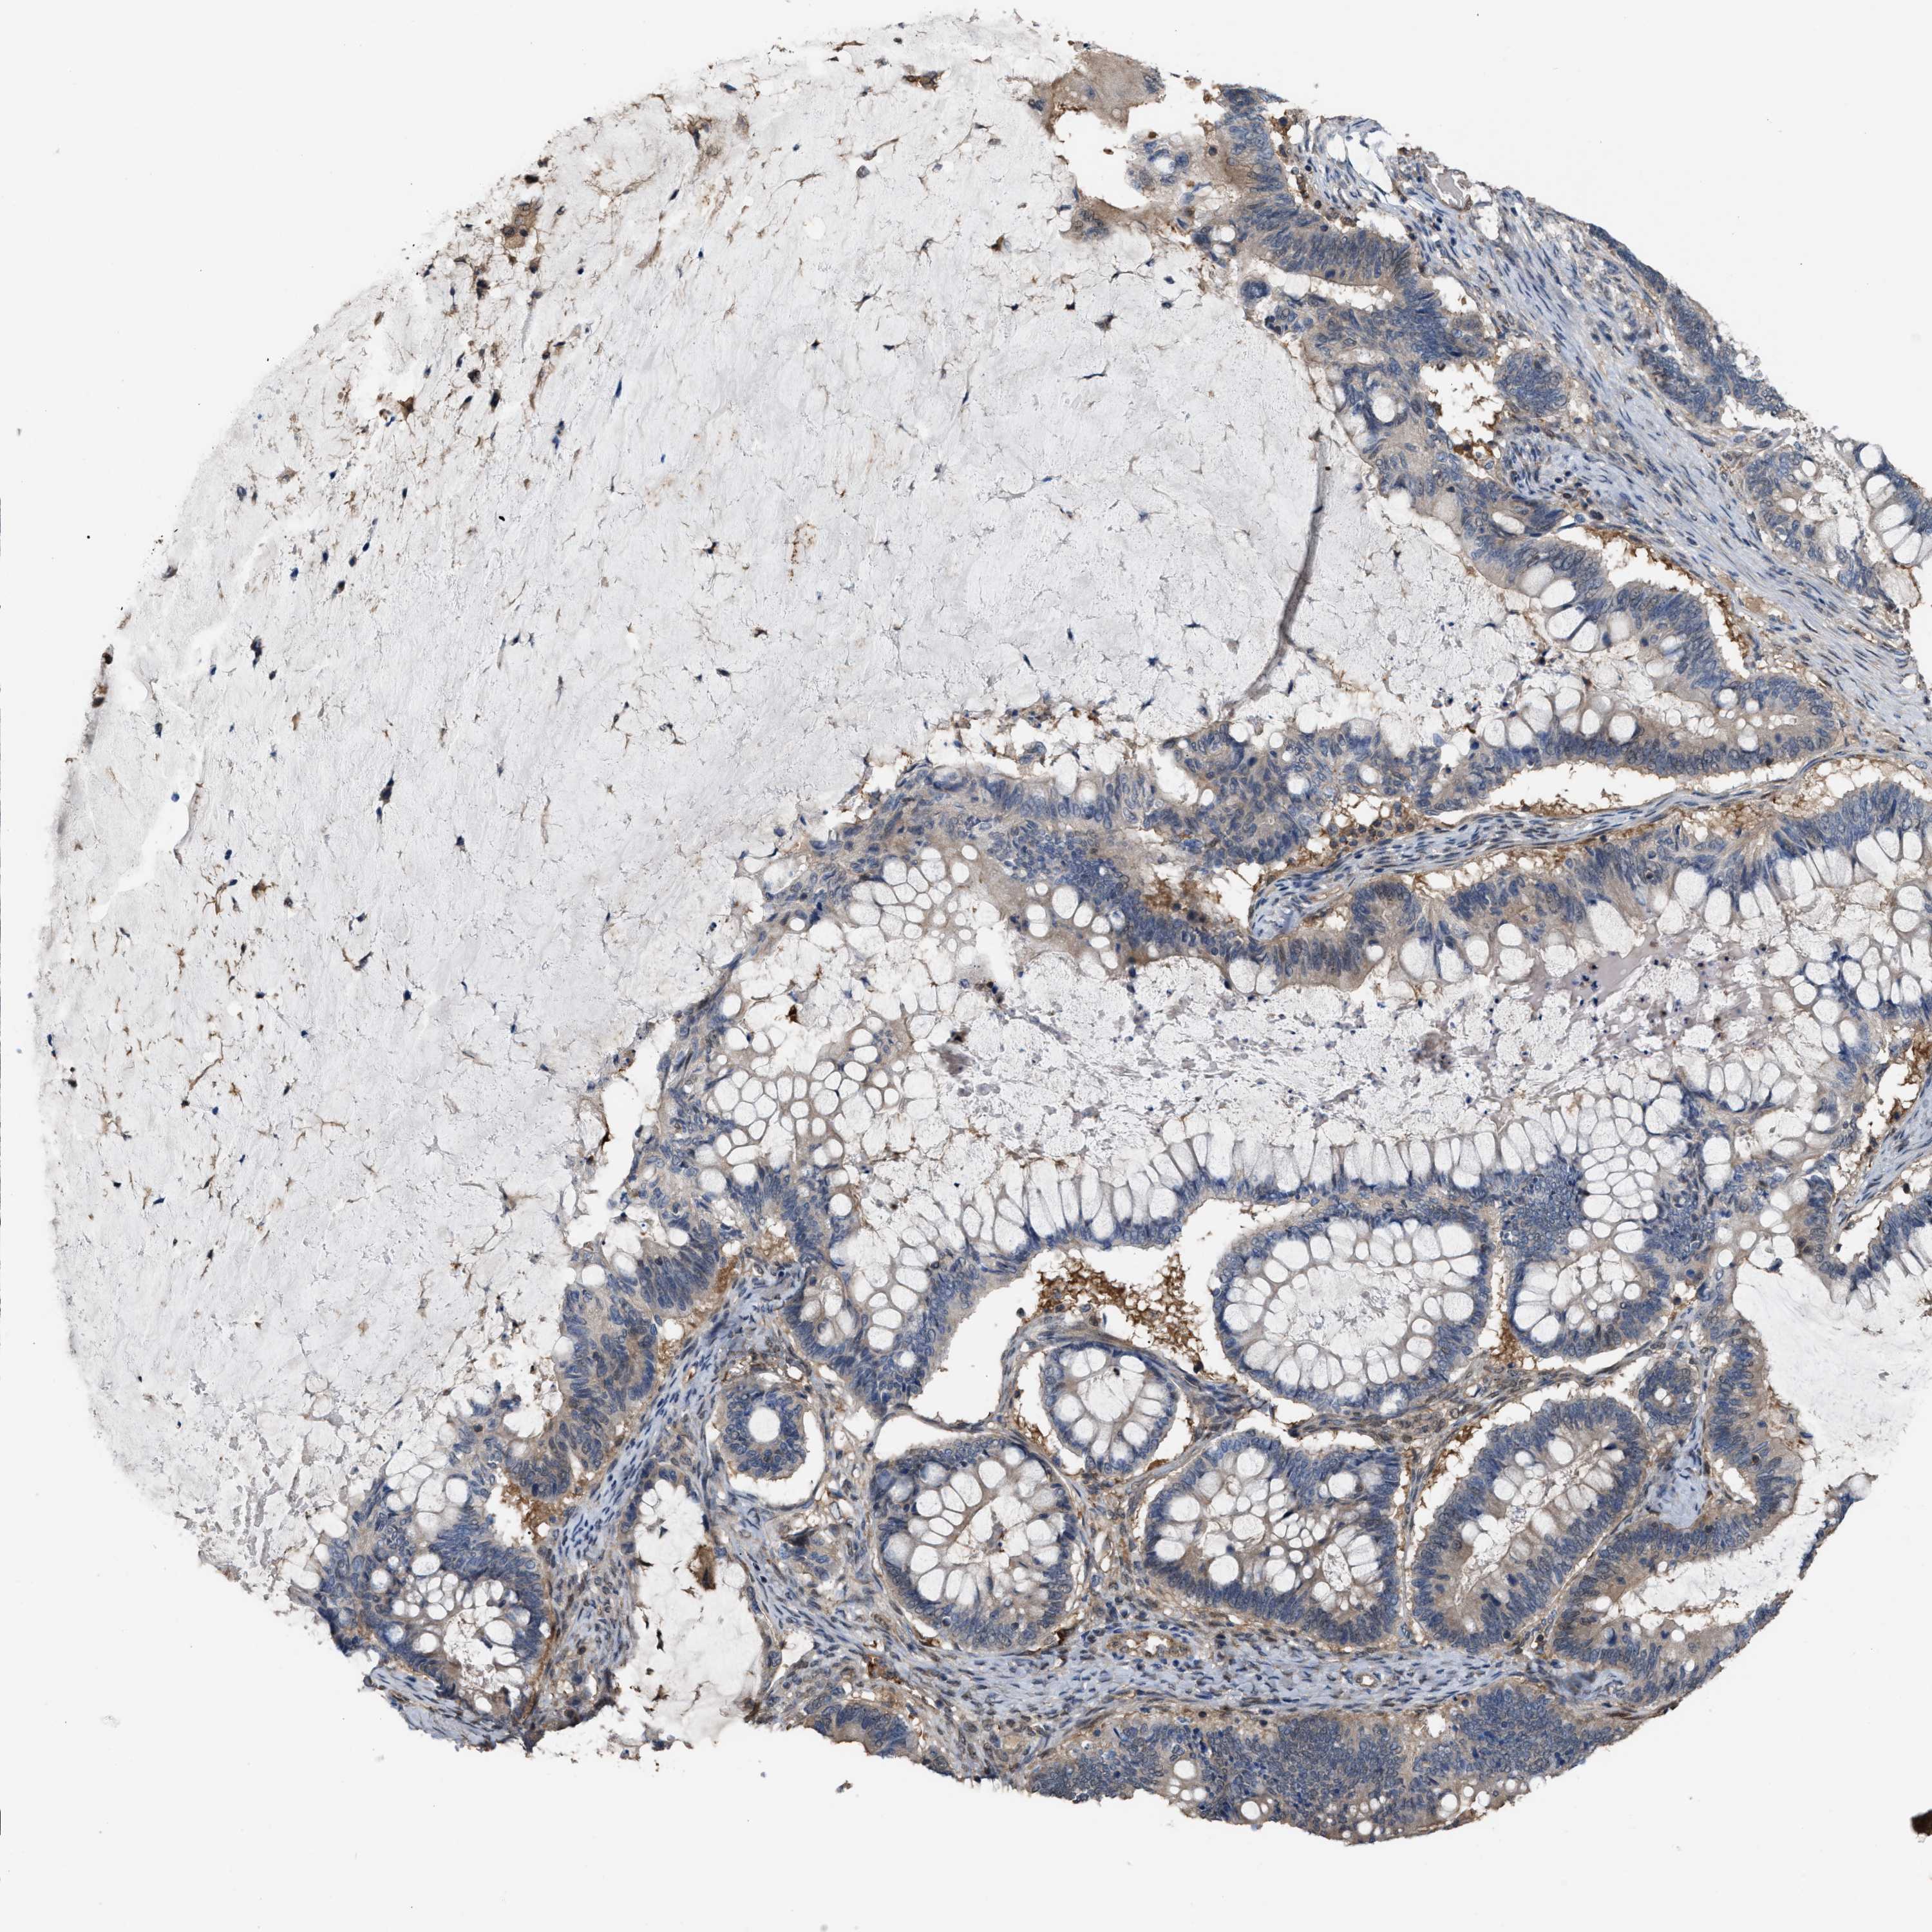

OVARIAN CANCER - Protein expressioni

A mouse-over function shows sample information and annotation data. Click on an image to view it in a full screen mode. Samples can be filtered based on level of antibody staining by selecting one or several of the following categories: high, medium, low and not detected. The assay and annotation is described here.

Note that samples used for immunohistochemistry by the Human Protein Atlas do not correspond to samples in the TCGA dataset.

Antibody stainingi

Antibody staining in the annotated cell types in the current human tissue is reported as not detected, low, medium, or high, based on conventional immunohistochemistry profiling in selected tissues. This score is based on the combination of the staining intensity and fraction of stained cells.

Each image is clickable and will lead to virtual microscopy that enables deeper exploration of all samples and also displays staining intensity scores, fraction scores and subcellular localization as well as patient and tissue information for each sample.

Antibody HPA019735

Staining

High

Medium

Low

Not detected

Intensity

Strong

Moderate

Weak

Negative

Quantity

>75%

75%-25%

<25%

None

Location

Nuclear

Cytoplasmic/membranous

Cytoplasmic/membranous,nuclear

Cystadenocarcinoma, serous, NOS

Carcinoma, endometroid

Cystadenocarcinoma, mucinous, NOS

Carcinoma, NOS